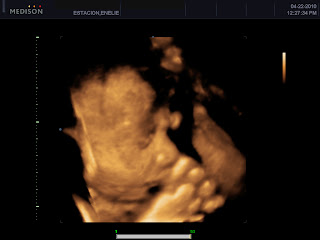

We opted to avail of In My Womb's Pearl Package (the cheapest 3D/4D package they have). I had my first scan last April 18 but since my baby is presented in a Frank breech position (and his face is covered by his hands and legs), the doctor had to reschedule me for a rescan to get a clearer view of my baby's face.

April 21. More than 30 minutes of lying uncomfortably on my side. Seeing him twist and turn, frown and smile, cover his face and pick his nose. Here he is:

Almost everyone (including my family, his family, my friends and colleagues, his friends and colleagues, even the doctor) agrees that he looks like Irvin. On the other hand, Irvin disagrees and says that our baby looks like me, but I think he says so just so I would not feel sad hahaha! Me? I'm happy having a little version of Irvin :D